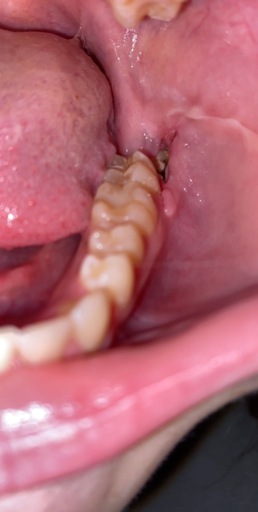

I had all 4 of my wisdom teeth removed 6 days ago. I had stitches on my two bottom ones which have seemed to dissolve on their own. I still have some mild aching, pain and soreness on both sides of my jaw, is that normal? And are they healing properly?